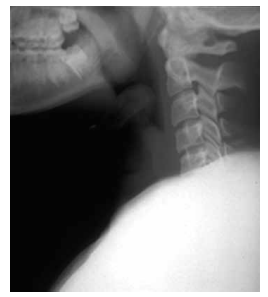

Criança de 4 anos apresenta febre (38 ºC), estridor e dispneia leve há 3 dias. Foi realizada a radiografia a seguir.

Qual o principal agente causador desse quadro clínico?